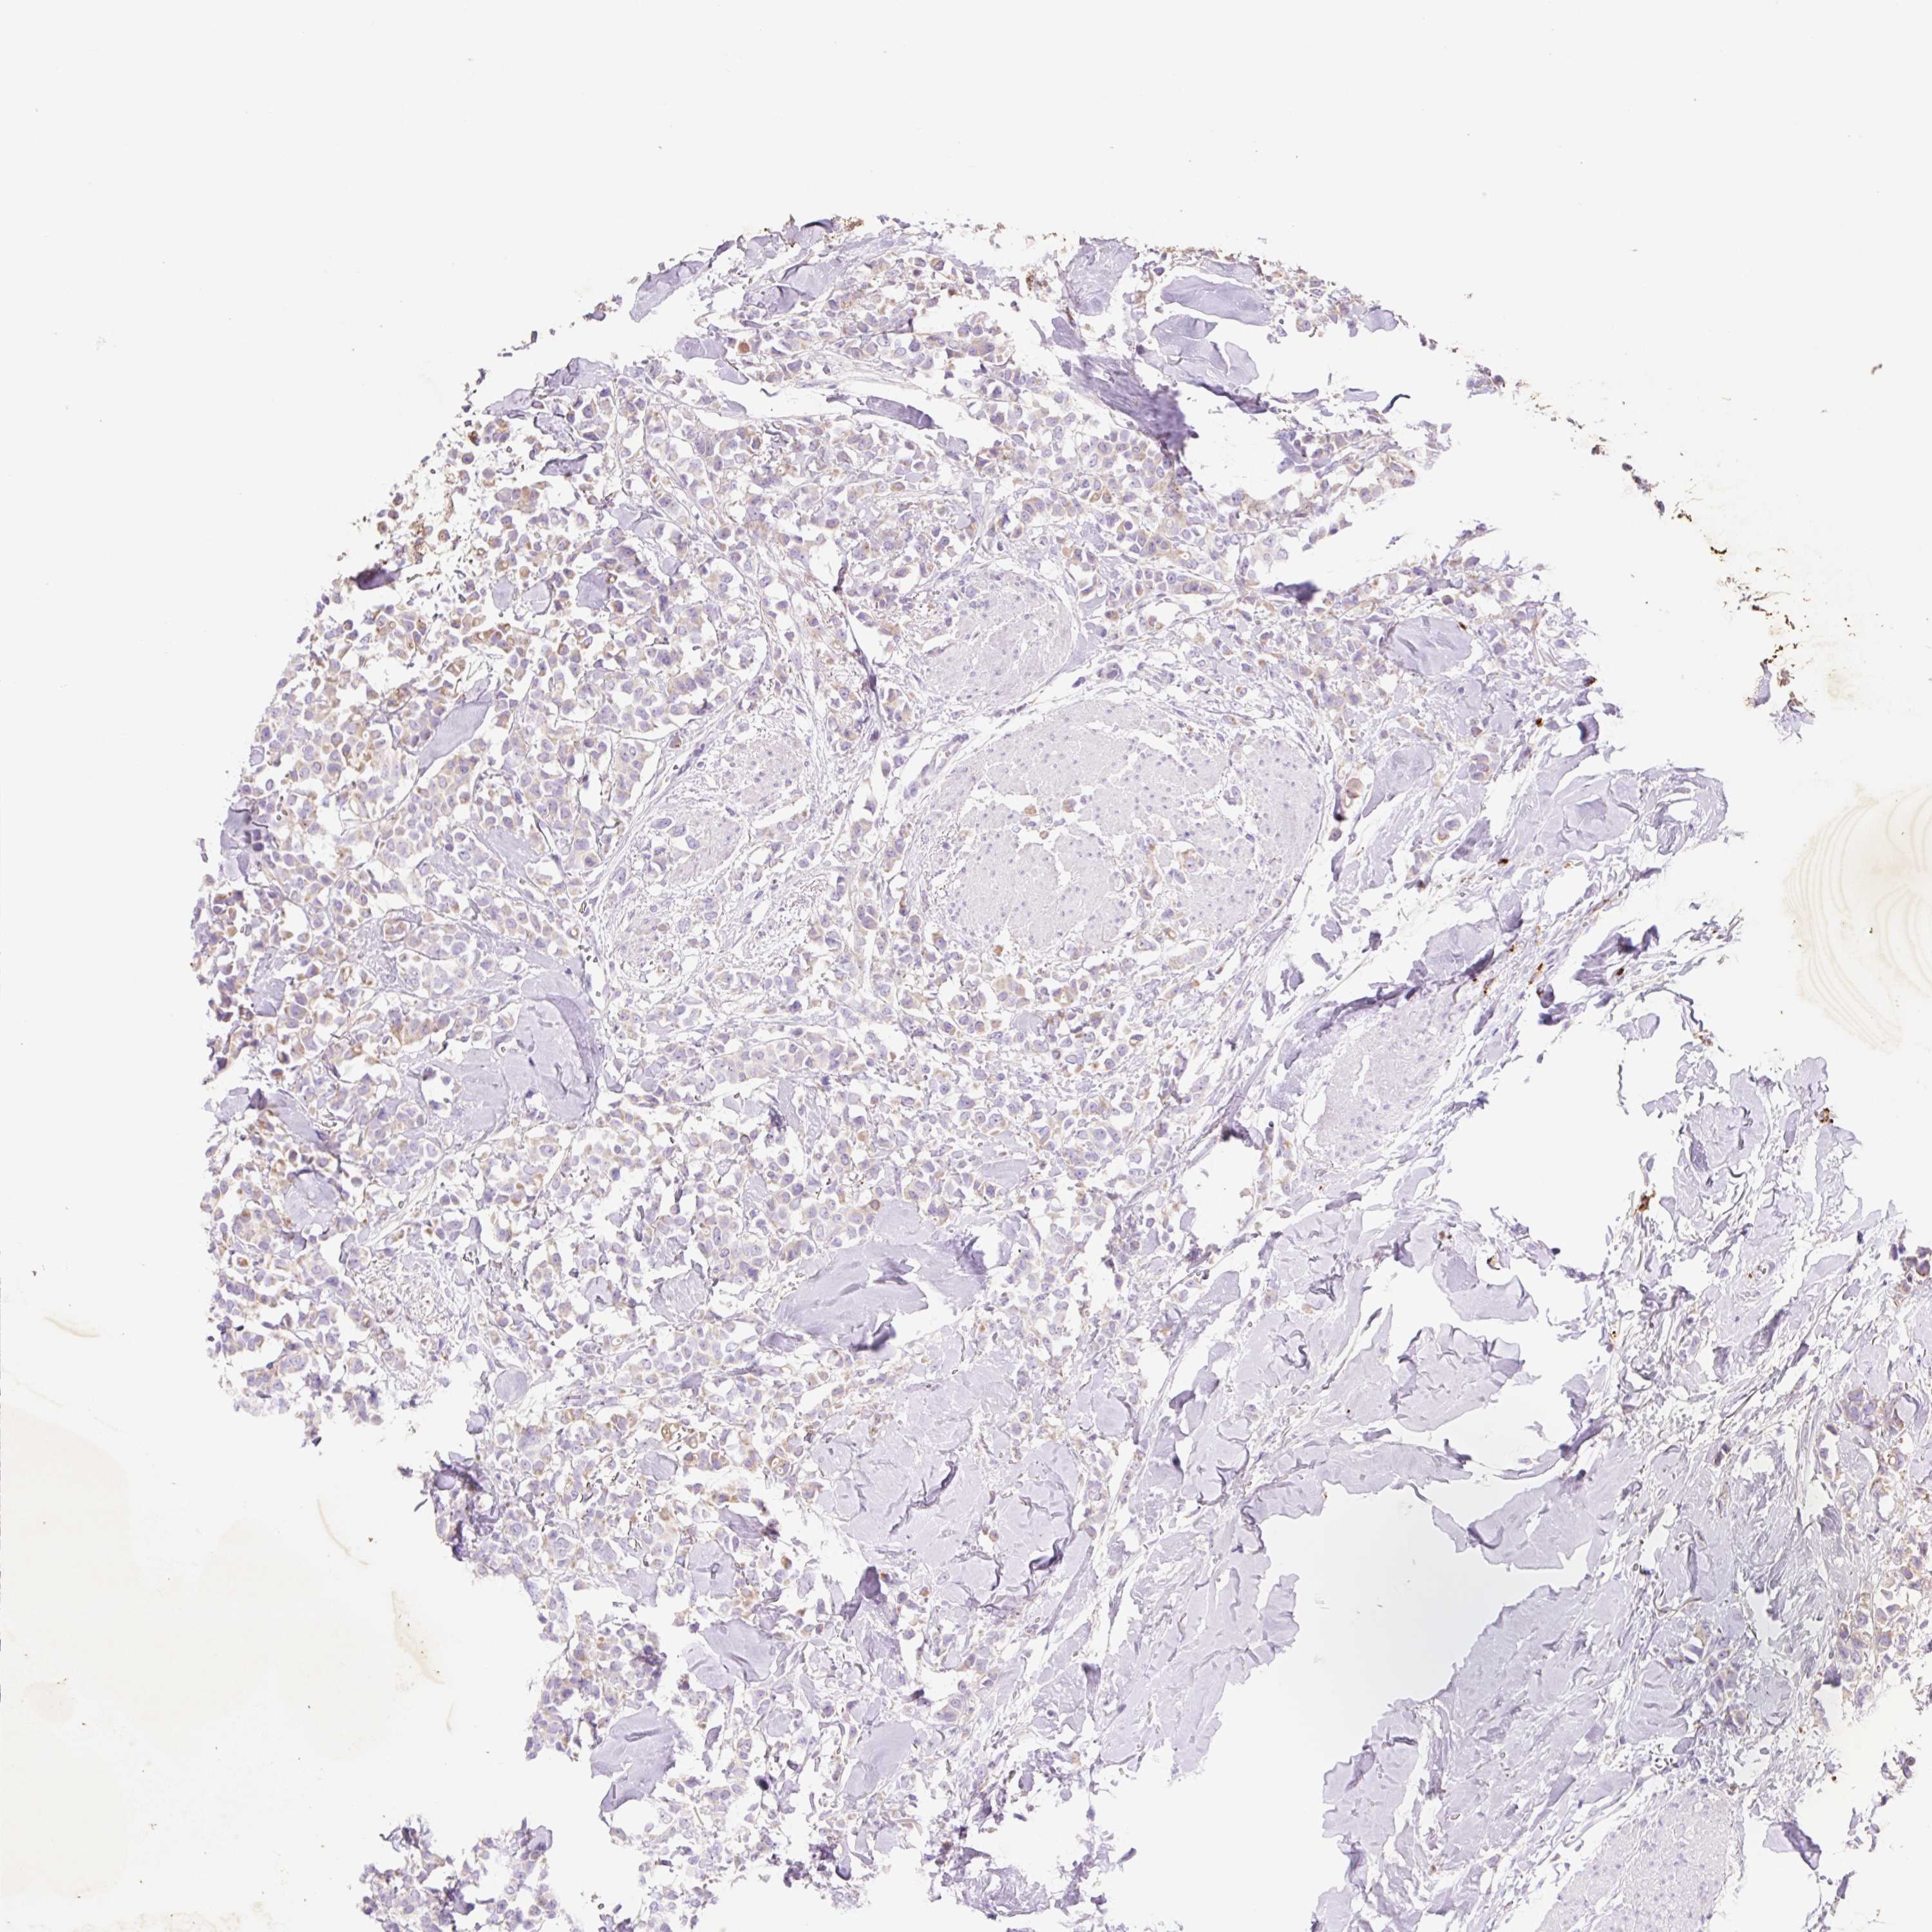

CANCER BREAST CANCER Show tissue menu

BRCA TCGA BRCA VALIDATION PROTEIN EXPRESSION

Breast cancer

Human cancer

Breast invasive carcinoma